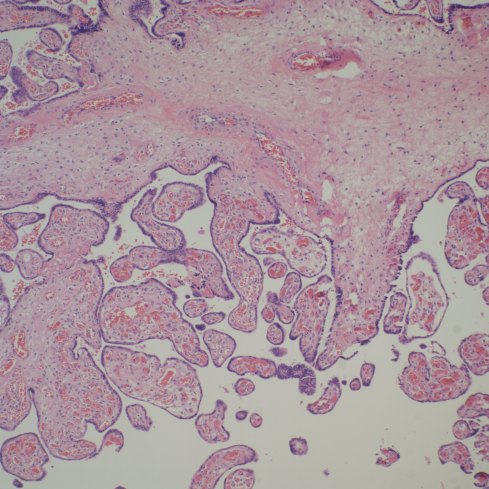

Altshuler’s paper found that 27% of cases had villitis of unknown etiology. This is certainly a finding that routine placental examination appears to support (fig 3). In practice, if I see a focus of larger, hypervascular villi, this is a clue to look for villitis and avascular villi. I rationalize this hypervascularity as due to increased blood flow in a segment of a stem villus in which other segments have capillary occlusion. The villi with shunted blood flow adapt over time by producing more capillaries. A similar adaption to high flow can be seen in diffuse hypervascularity of villi in the recipient twin in twin-to-twin-transfusion in which the pregnancy was prolonged with serial amniocentesis[10].